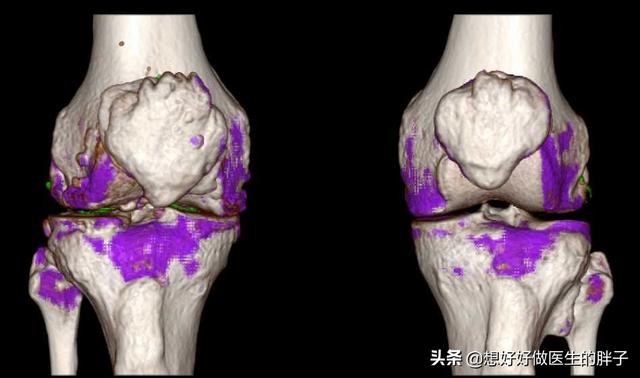

どうか、私たちは科学を信じなければならない。病院に行きたくても行きたくなくても、病院はそこにある。痛風かもしれないと思ったら、病院で専門的な検査を受けること。二重エネルギーCT、血中尿酸検査、超音波検査を行う。これにより、体のある部分に尿酸塩結晶が沈着しているかどうかを特定し、痛風発作の可能性があるかどうかを判断するのに役立つ。やみくもに自己判断で自宅療養し、体調の遅れを招かないこと。。

第2段階は、例えば超音波検査で「ダブルトラックサイン」を検出したり、画像検査を行うことである。デュアルエナジーCTで尿酸塩沈着が見つかるなど、そしてX線検査で軟部組織の腫脹、軟骨辺縁の破壊、関節面の不整が認められる。!

痛風は画像診断で発見することができ、関節軟骨の「ダブルトラックサイン」関節液貯留、骨びらんなどの有無、腎機能指標でも診断することができる。